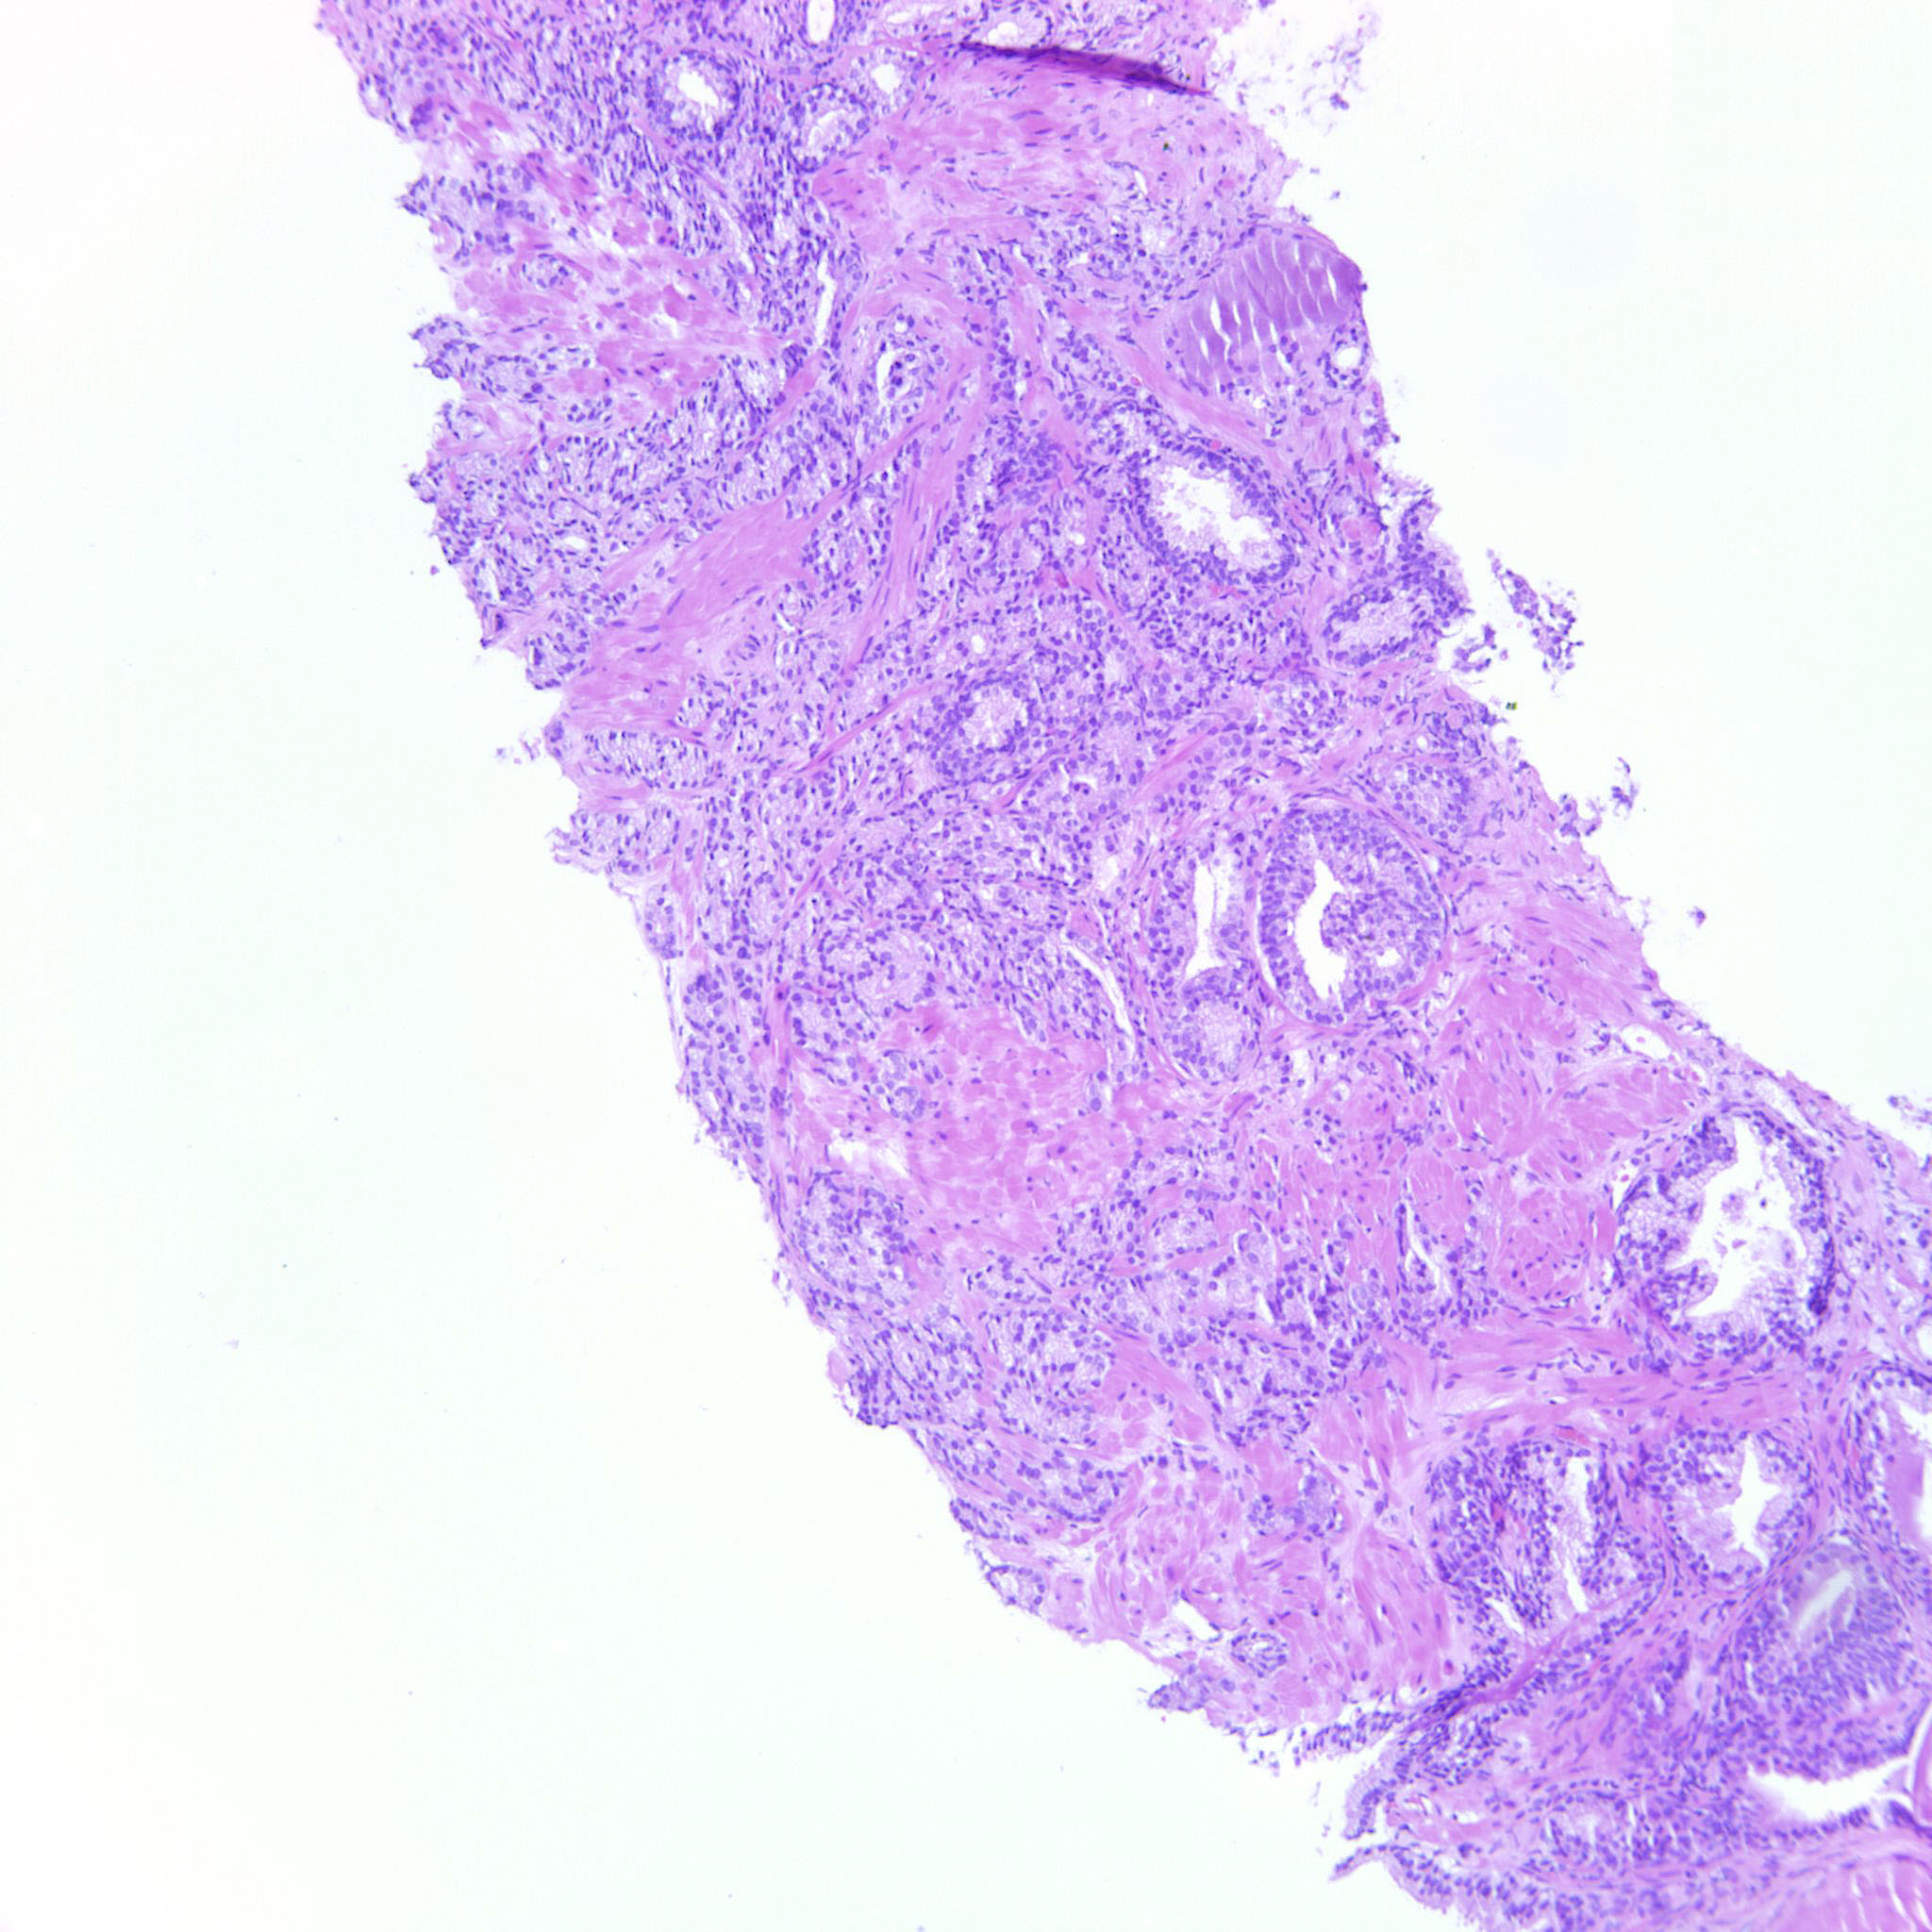

Prostate cancer grading

Case ID: 122